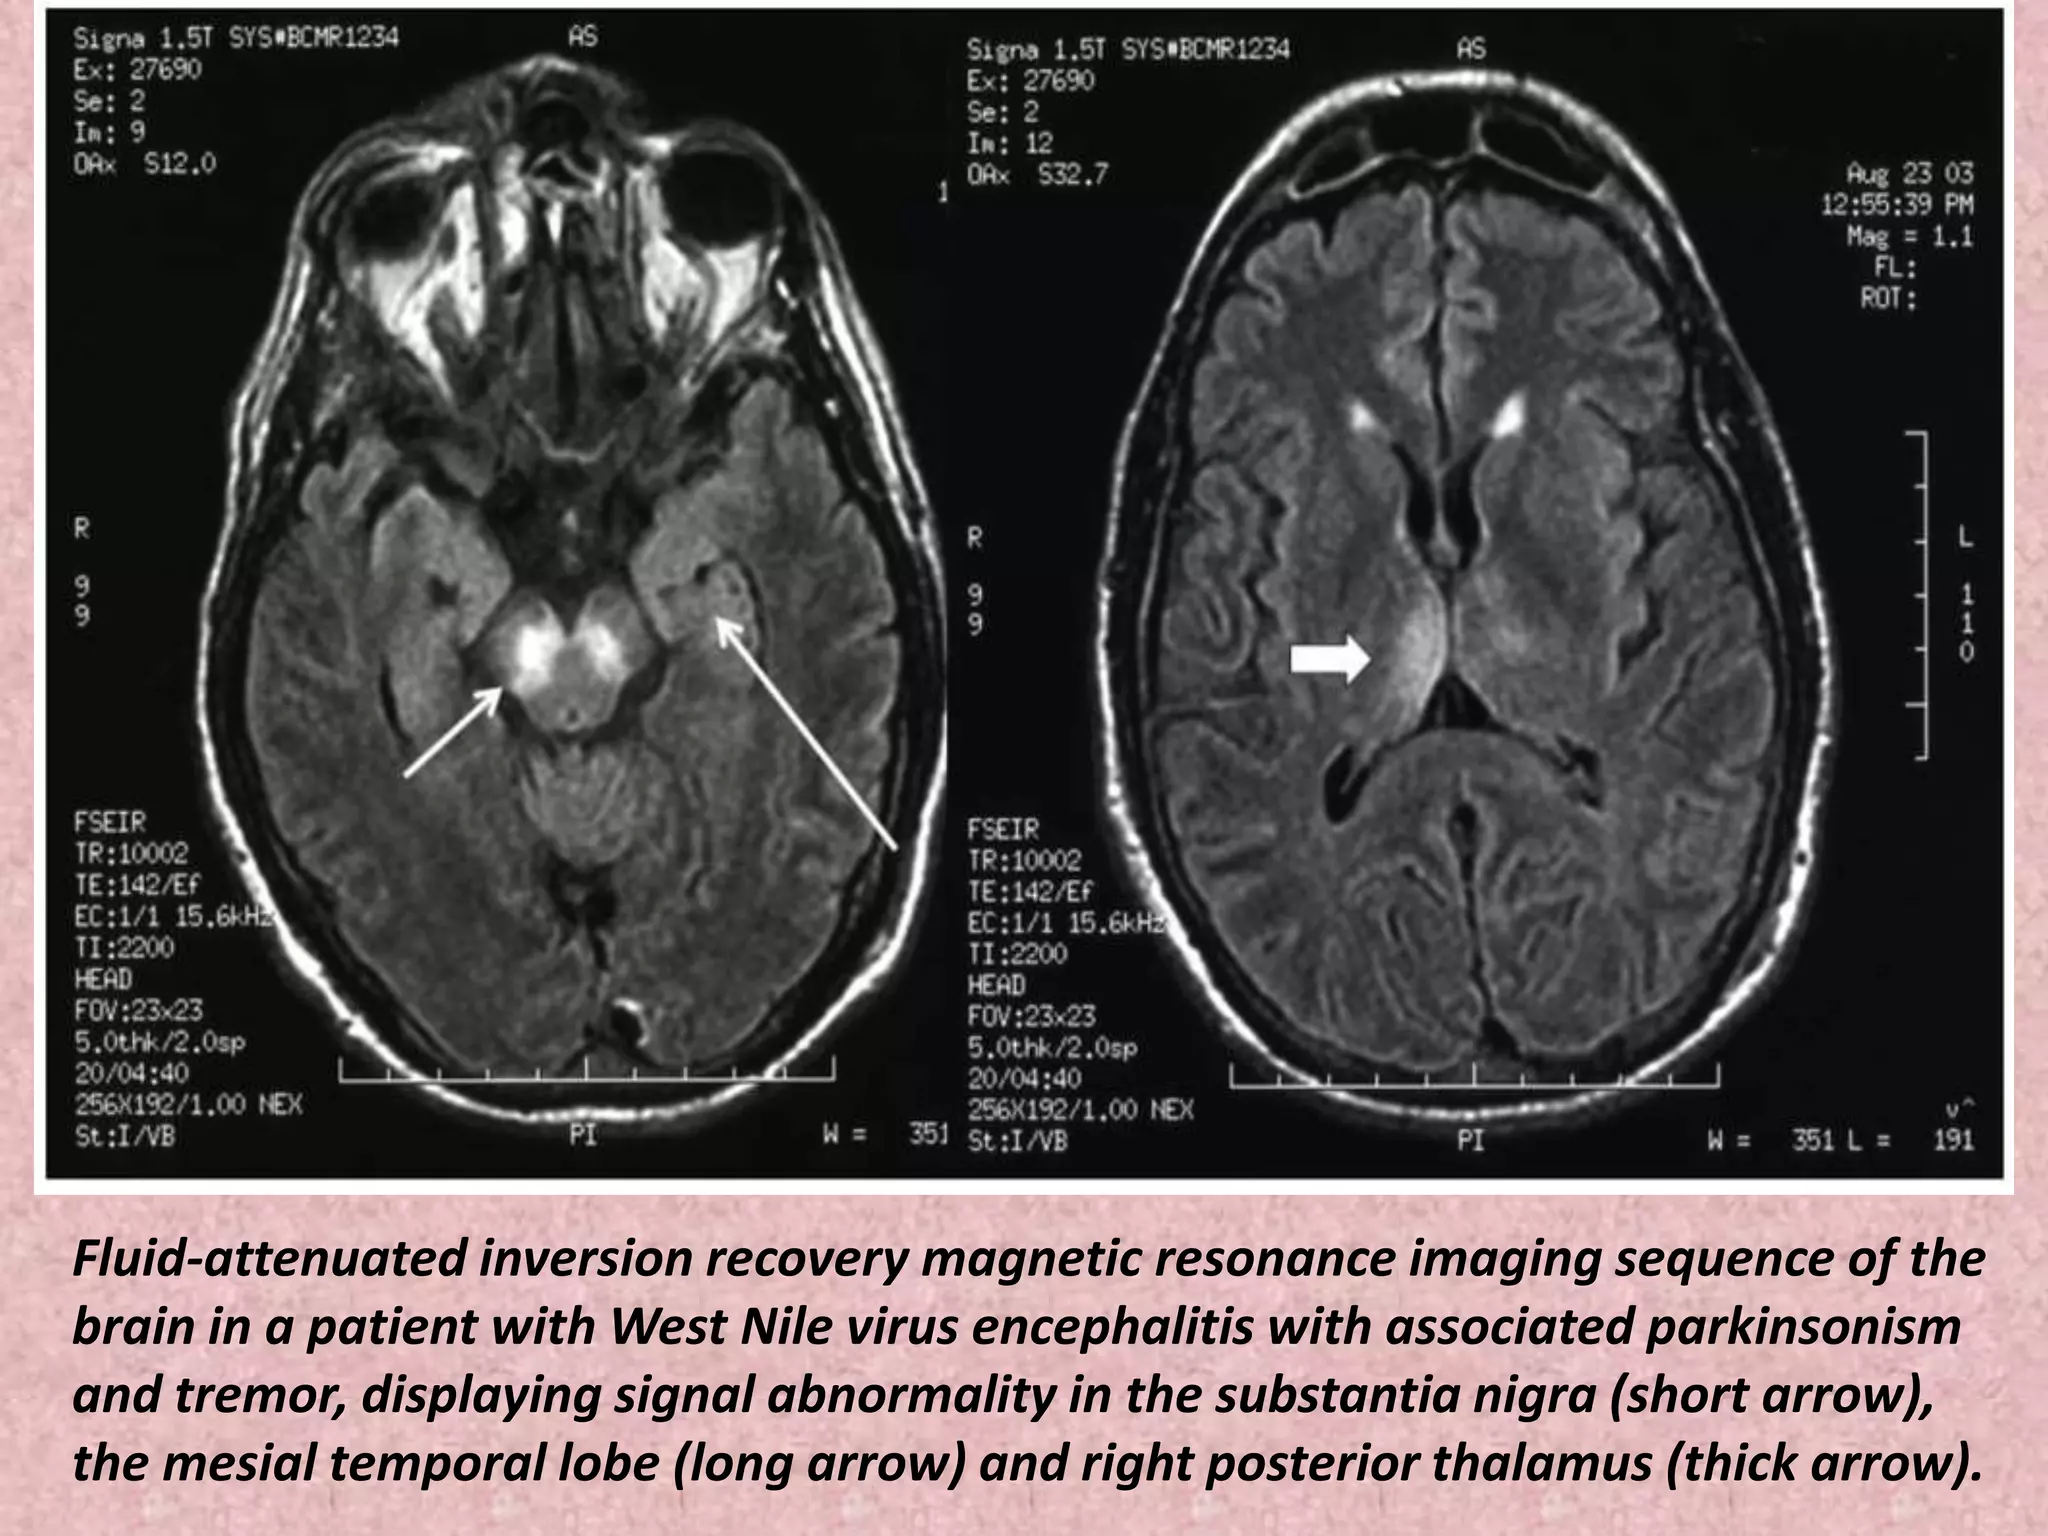

Fluid-attenuated inversion recovery magnetic resonance imaging sequence of the

brain in a patient with West Nile virus encephalitis with associated parkinsonism

and tremor, displaying signal abnormality in the substantia nigra (short arrow),

the mesial temporal lobe (long arrow) and right posterior thalamus (thick arrow).

Fluid-attenuated inversion recoverymagnetic resonance imaging sequence of the brain in a patient with West Nile virus encephalitis with associated parkinsonism and tremor, displaying signal abnormality in the substantia nigra (short arrow), the mesial temporal lobe (long arrow) and right posterior thalamus (thick arrow).